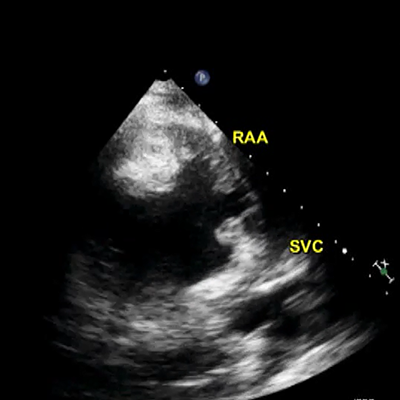

TEE: thrombus in the LAA

Mitral valve is only mildly thickened and left atrial appendage is clear

Mitral valve thickened and left atrial appendage is clear

Mitral valve is only mildly thickened and left atrial appendage is clear